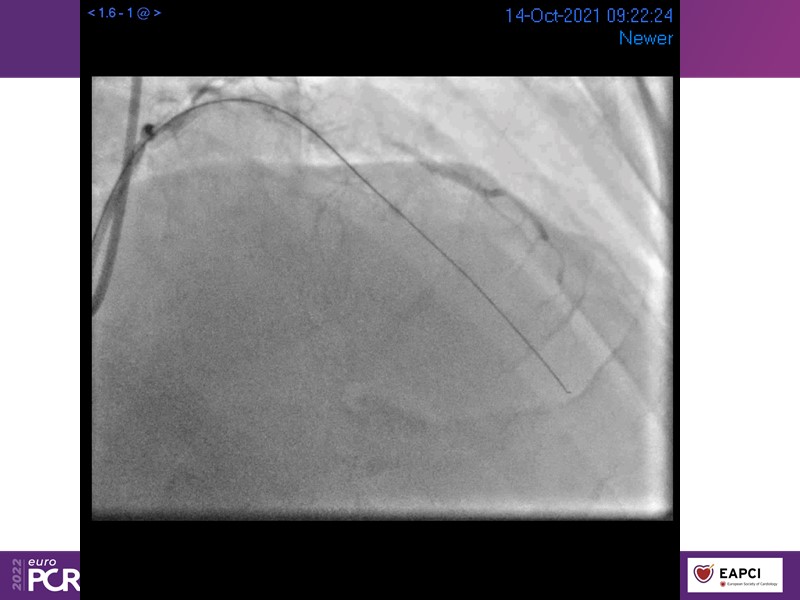

- To find out more about the application and mechanism of a sirolimus coated balloon for coronary artery disease treatment with case presentations in complex settings